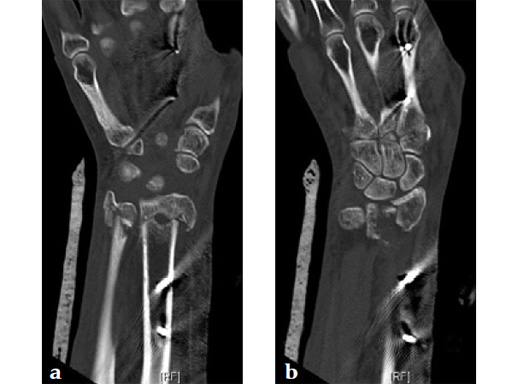

The anatomical plate design allows for very distal plate placement. CT scans were used to verify the fit of the precontoured plate. Bendable outriggers aid in adjusting the precontoured plate to specific anatomical need and individual variations.

The second distal screw row provides for superior fixation stability of fragments, eg, radial styloid, and especially the most ulnar corner of the lunate fossa.

Fig 2a-b Comparison of anatomical bend and screw placement of volar rim DR plate (a) and DR juxta-articular plate (b).